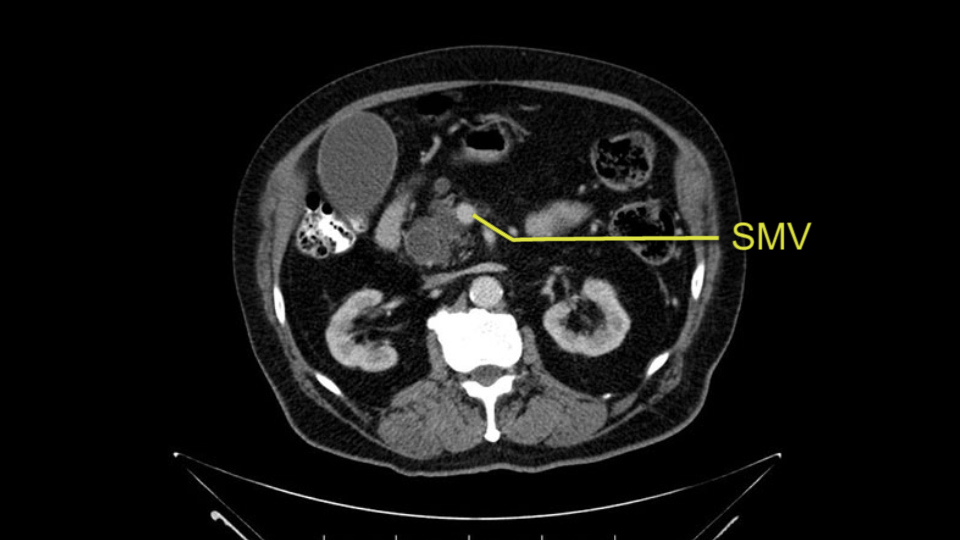

The next item that I would look at: the issue would be the vessels and usually start at the portal vein, watch the portal vein, follow it down, down-down-down to the neck of the pancreas - which is here - and there’s no impingement by tumor, which is great. The SMV and the splenic vein, which is here. The splenic vein junction is normal, which is great.

Then look at the first jejunal branch - which is this thing here - this little branch which goes under the SMA. It’s something that we’ve just started appreciating over the past few years and the reason for that is: there’s two or three small branches that come out of the uncinate into the the first jejunal and it’s a fairly inevitable part of the operation where there’s some bleeding. As long as you’re cognizant of what’s happening, it’s no reason to panic and that kind of bleeding will eventually stop or can be stopped but it’s not easy because these little vessels are fragile from the uncinate to the first jejunal. So I do focus on that and it’s pretty consistent I’d say 9 times out of 10, people have that first jejunal.

The other thing I look at is the gastroepeiploic arcade- which is this thing here- which is where the gastroepeiploic vein joins the portal vein. I call it the gateway to the neck of the pancreas because you pretty much have to divide it to get to the neck. The middle colic vein usually drains either into it or nearby. I think we’re seeing it here. Again,that can be divided and I usually divide those two and it helps me get under the neck. Again, there’s no issues here with the tumor so it’s nice from that perspective. If I was concerned about the vein, which I’m not here, I would go to the coronal view. It’s a nice way to look at the vein on just a couple of cuts and you can see a beautiful view of it here. There’s the portal vein, there’s the head of the pancreas. There’s the tumor. It’s a little closer here than it looks on the other one. I doubt it’s involved. If it’s touching, it may not be invading it but even if it was, it's a short segment. Anyways, there’s the SMV there’s the splenic vein, and everything looks good. You can see the stent. I ignore the stent. It’s the most dramatic looking thing in the picture but it’s actually the least important.

Then either through the coronal or the axial, I’ll do both. Look at the SMA -which is here- I had already looked at it and I don’t see any involvement. There’s the SMA with a nice fat plane between the SMA and the tumor. Over here you can see on the axial, there’s the SMA. Everything on the right side of the SMA has got some nice black around it, which is fat, which means probably no tumor [no tumor, no tumor]. Follow it up to the origin, coming off the aorta. So those are the two technical things that I worry about: the SMA and the SMV.

The initial hepatic flexure mobilization and the Kocher procedure is then going to enable me to understand the uncinate process of this patient, which should not be a problem, again. But the initial pictures had shown a degree of touching. I would not even say involvement or abutment; a degree of touching with the superior mesenteric vein. So that would give me an early chance to assess how the superior mesenteric vein is in this patient. So this would be the initial slowing down moment.

The first steps of a pancreaticoduodenectomy involve ensuring the CT findings are correct: exploring for signs of metastatic disease, peritoneal implants involving the omentum or the undersurface of the diaphragm and if again this is confirmed exploration that there's no metastatic disease, I begin the mobilization and really determining the relationship of the tumor with the major visceral vessels. I start by an extended Kocher maneuver, identify the superior mesenteric vein below the neck of the pancreas. They’re very thin walled vessels and as you're dissecting you have to use the ultimate care and meticulously dissect the superior mesenteric vein, ligate the anterior branches and begin the dissection from below to under the neck of the pancreas. At this point, if there's no reason to be concerned about whether there is any vascular invasion below, I usually take the gallbladder down. I mobilize the common hepatic duct above the insertion of the gallbladder. This patients already has a stent in place. So I would divide the bile duct at this point. This facilitates the dissection of the anterior surface of the portal vein and as I would expect looking at this imaging that there is nothing to be concerned about in terms of vascular involvement.